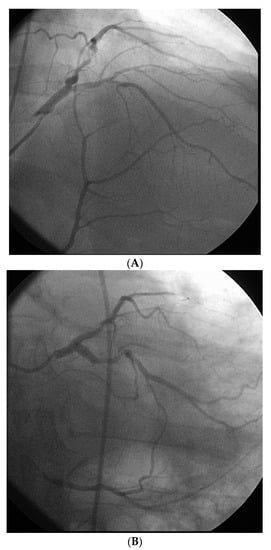

Figure 2.

Example of an ideal case for robotic PCI. These images are from a 72 year-old with unstable angina referred to our hospital for intervention. Diagnostic catheterization showed moderate disease in the LAD (A) but with fractional flow reserve of 0.65 and severe disease of the LCX (B) with chronic occlusion of the RCA. The LAD and LCX were both treated successfully robotically with post-stent images shown in (C).